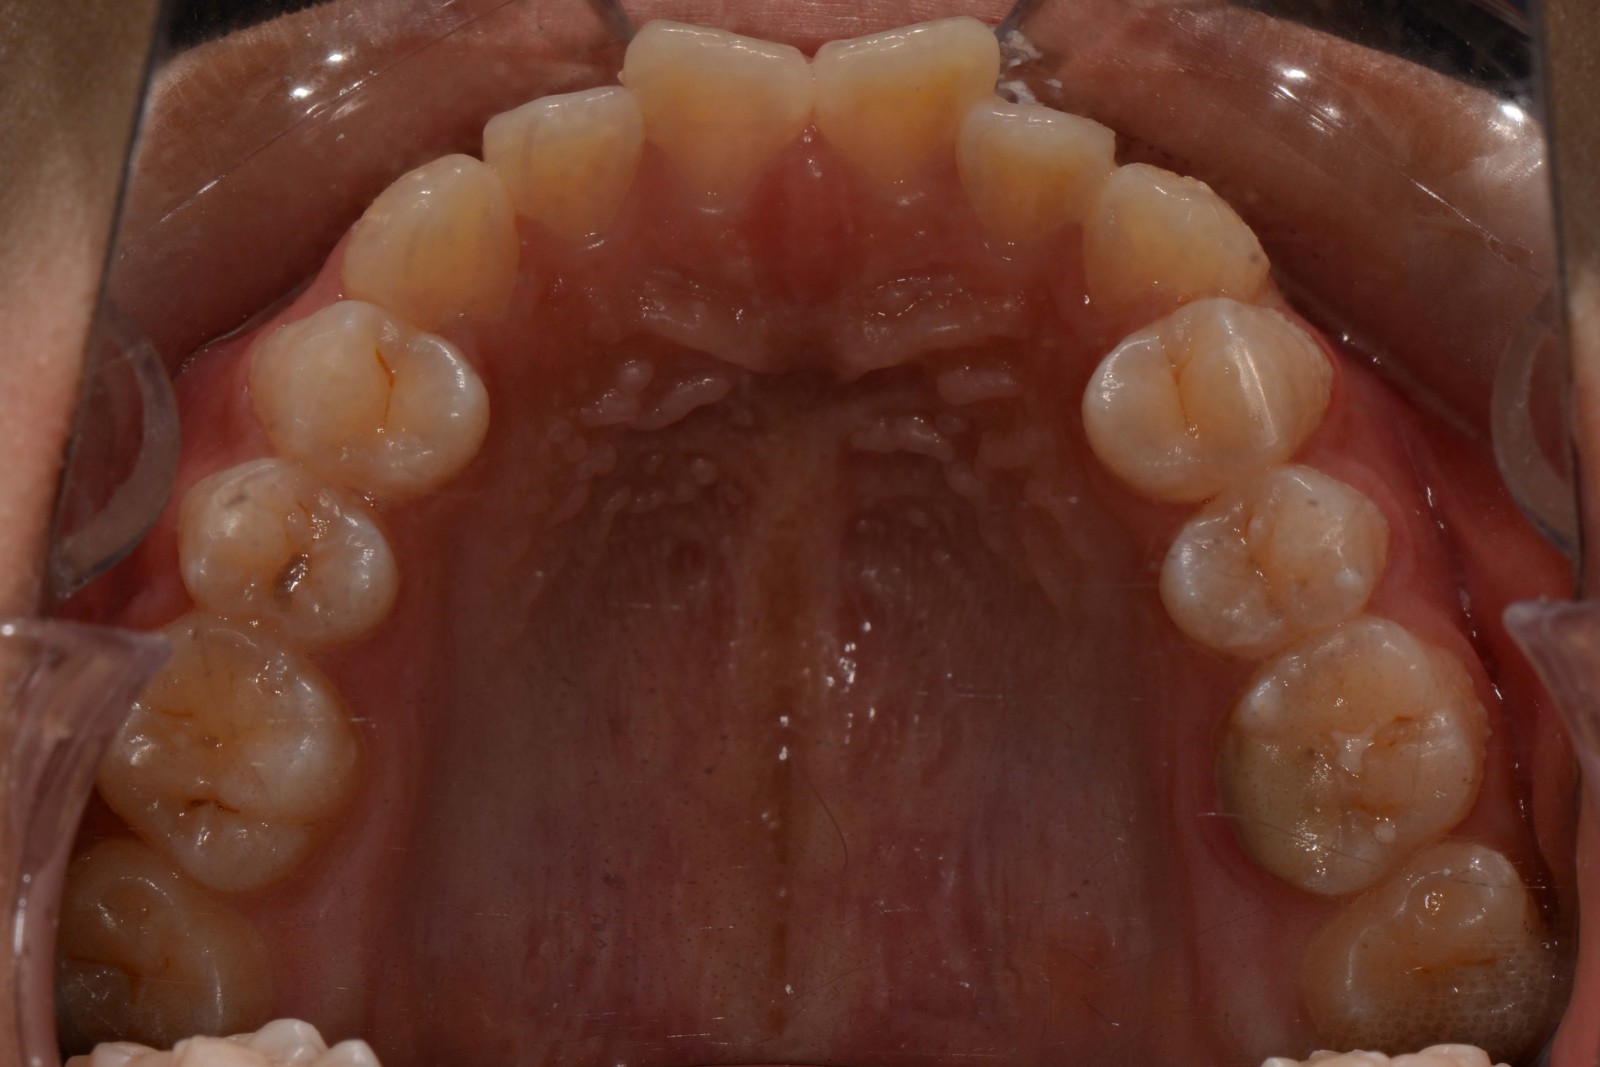

患者:14岁女性

前牙区开颌3mm

诊断:安氏II类错颌畸形  开颌

矫治前: